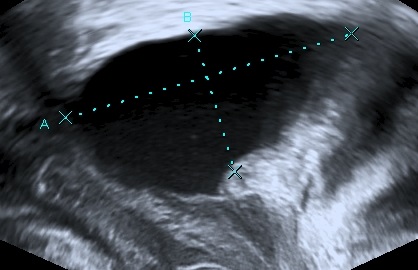

Dietz et al. using translabial ultrasound proposed the following formula in 2012:

Postvoid Residual Bladder Volume (ml) =

Height x Depth x 5.6

Dietz H.P. et al, 2012.

It is fairly accurate, simple and thus our method of preference.